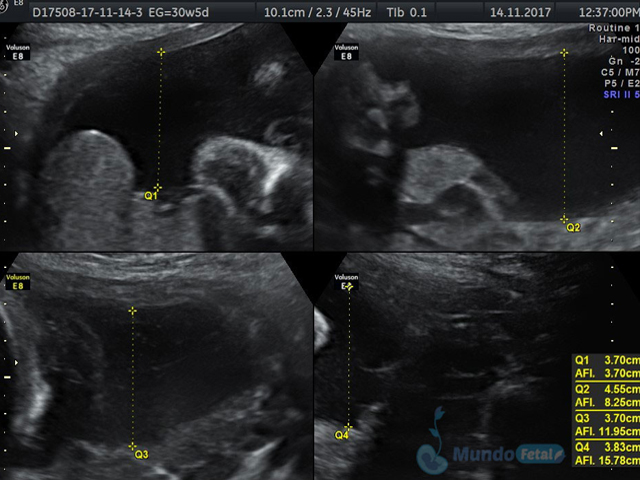

Se recomienda de 32-34 semanas, realizando valoración de crecimiento armónico (4 medidas específicas), valoración anatómica, líquido amniótico, flujos sanguíneos fetales y placentarios perfilando el bienestar fetal hacia el final de embarazo.